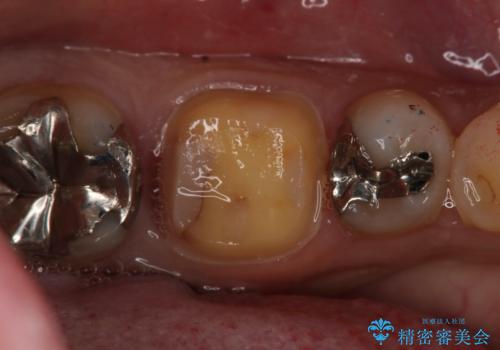

切削量などを考慮し、フルジルコニアクラウンでの治療を選択しました。

う蝕が歯髄に近接していたので麻酔が切れた後に痛みなどの症状が出る可能性をお伝えしています。

う蝕が深く切削量が多くなりましたが痛みなどは起きなかったので、予定通りフルジルコニアクラウンでの治療で進めました。